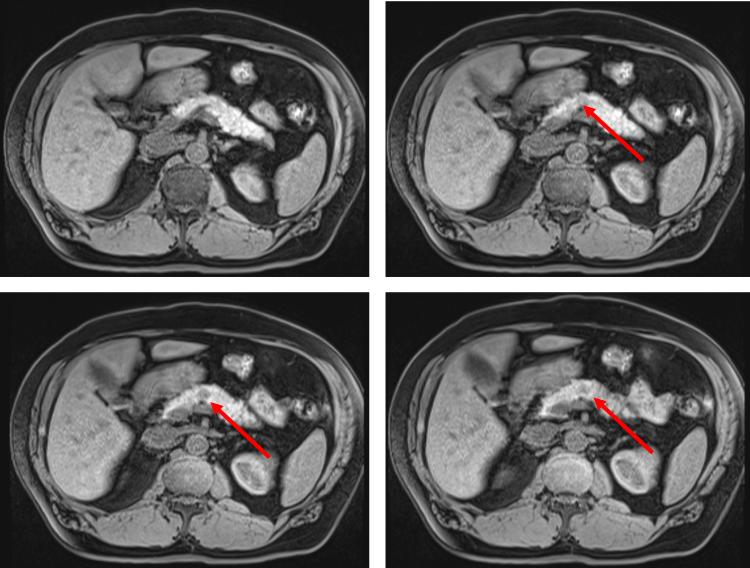

Liver parenchyma that resides outside of the normal hepatic confines is defined as accessory liver if in communication with the native biliary tree, or ectopic liver (EL) if it is not. EL can develop in a variety of tissues, including but not limited to the gallbladder, the hepatic ligaments, the pancreas, and retroperitoneum. EL has an increased propensity for malignant degeneration resulting in hepatocellular carcinoma (HCC). A 67-year-old Korean male presented with epigastric discomfort and was found to have an elevation in his transaminases. Cross-sectional imaging demonstrated a 1.3 cm solid mass in the body of the pancreas with features concerning for either a pancreatic ductal adenocarcinoma or pancreatic neuroendocrine tumor. Subsequent endoscopic ultrasound and fine needle aspiration demonstrated cells of epithelial origin with hepatocellular differentiation. A robotic-assisted distal pancreatectomy and splenectomy was performed with final pathology demonstrating a well-differentiated HCC. EL with malignant degeneration resulting in HCC requires surgical excision. The majority of patients reported with EL resulting in HCC in the pancreas have had the tumors located in the body and tail. Therefore, definitive treatment requires distal pancreatectomy and splenectomy. Herein, we describe the presentation, workup, and definitive treatment of HCC arising in the pancreas.

位于正常肝脏边界之外的肝实质,如果与天然胆管树相通,则定义为副肝;如果不相通,则定义为异位肝(EL)。EL可发生于多种组织,包括但不限于胆囊、肝韧带、胰腺和腹膜后。EL发生恶性变导致肝细胞癌(HCC)的倾向增加。一名67岁的韩国男性因上腹部不适就诊,发现转氨酶升高。横断面成像显示胰腺体部有一个1.3厘米的实性肿块,其特征提示为胰腺导管腺癌或胰腺神经内分泌肿瘤。随后的内镜超声和细针穿刺显示为具有肝细胞分化的上皮来源细胞。行机器人辅助远端胰腺切除术和脾切除术,最终病理显示为高分化HCC。发生恶性变导致HCC的EL需要手术切除。大多数报道的胰腺EL导致HCC的患者,肿瘤位于体部和尾部。因此,明确的治疗需要远端胰腺切除术和脾切除术。在此,我们描述了胰腺HCC的临床表现、检查和明确治疗。